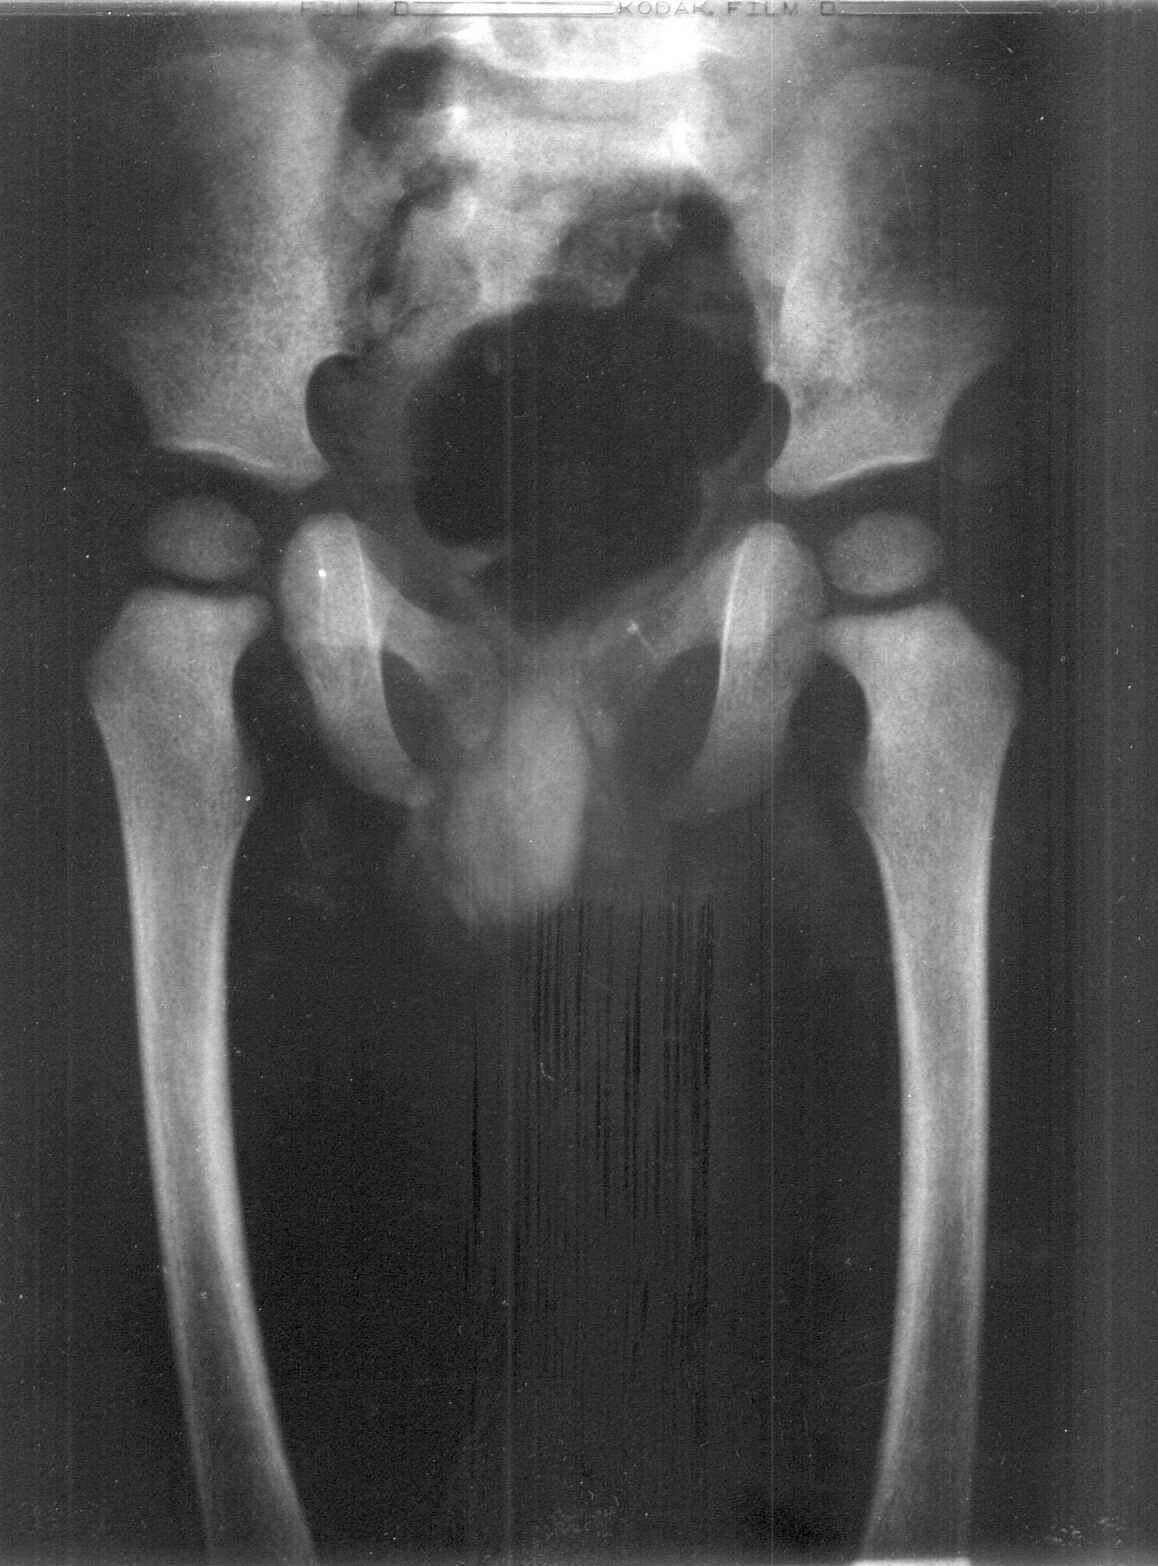

Age estimation in the living - Some medicolegal considerations, by Anil Aggrawal, India [Vol 1, No. 2 : July - December 2000]